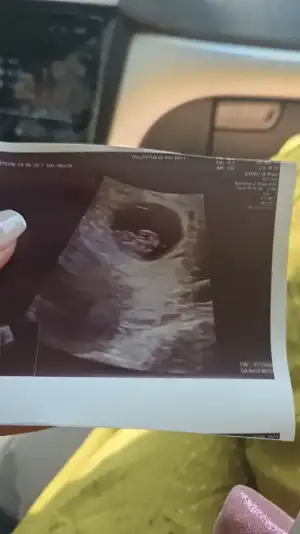

Kız gibi geldi bana sağlıkla gelsınMrb bebegimin cinsiyetini merak ediyorum bilen var mi acaba???

Baya erkek gibi duruyorMrb bebegimin cinsiyetini merak ediyorum bilen var mi acaba???

Bana da oyle geliyo ama bi turlu emin olamiyorumBaya erkek gibi duruyor

2 bacak arasından bakıyorlar attığın fotoğrafta o kısım da var çıkıntı var orada sadece ben mi görüyorumBana da oyle geliyo ama bi turlu emin olamiyorum

Erkek benceMrb bebegimin cinsiyetini merak ediyorum bilen var mi acaba???